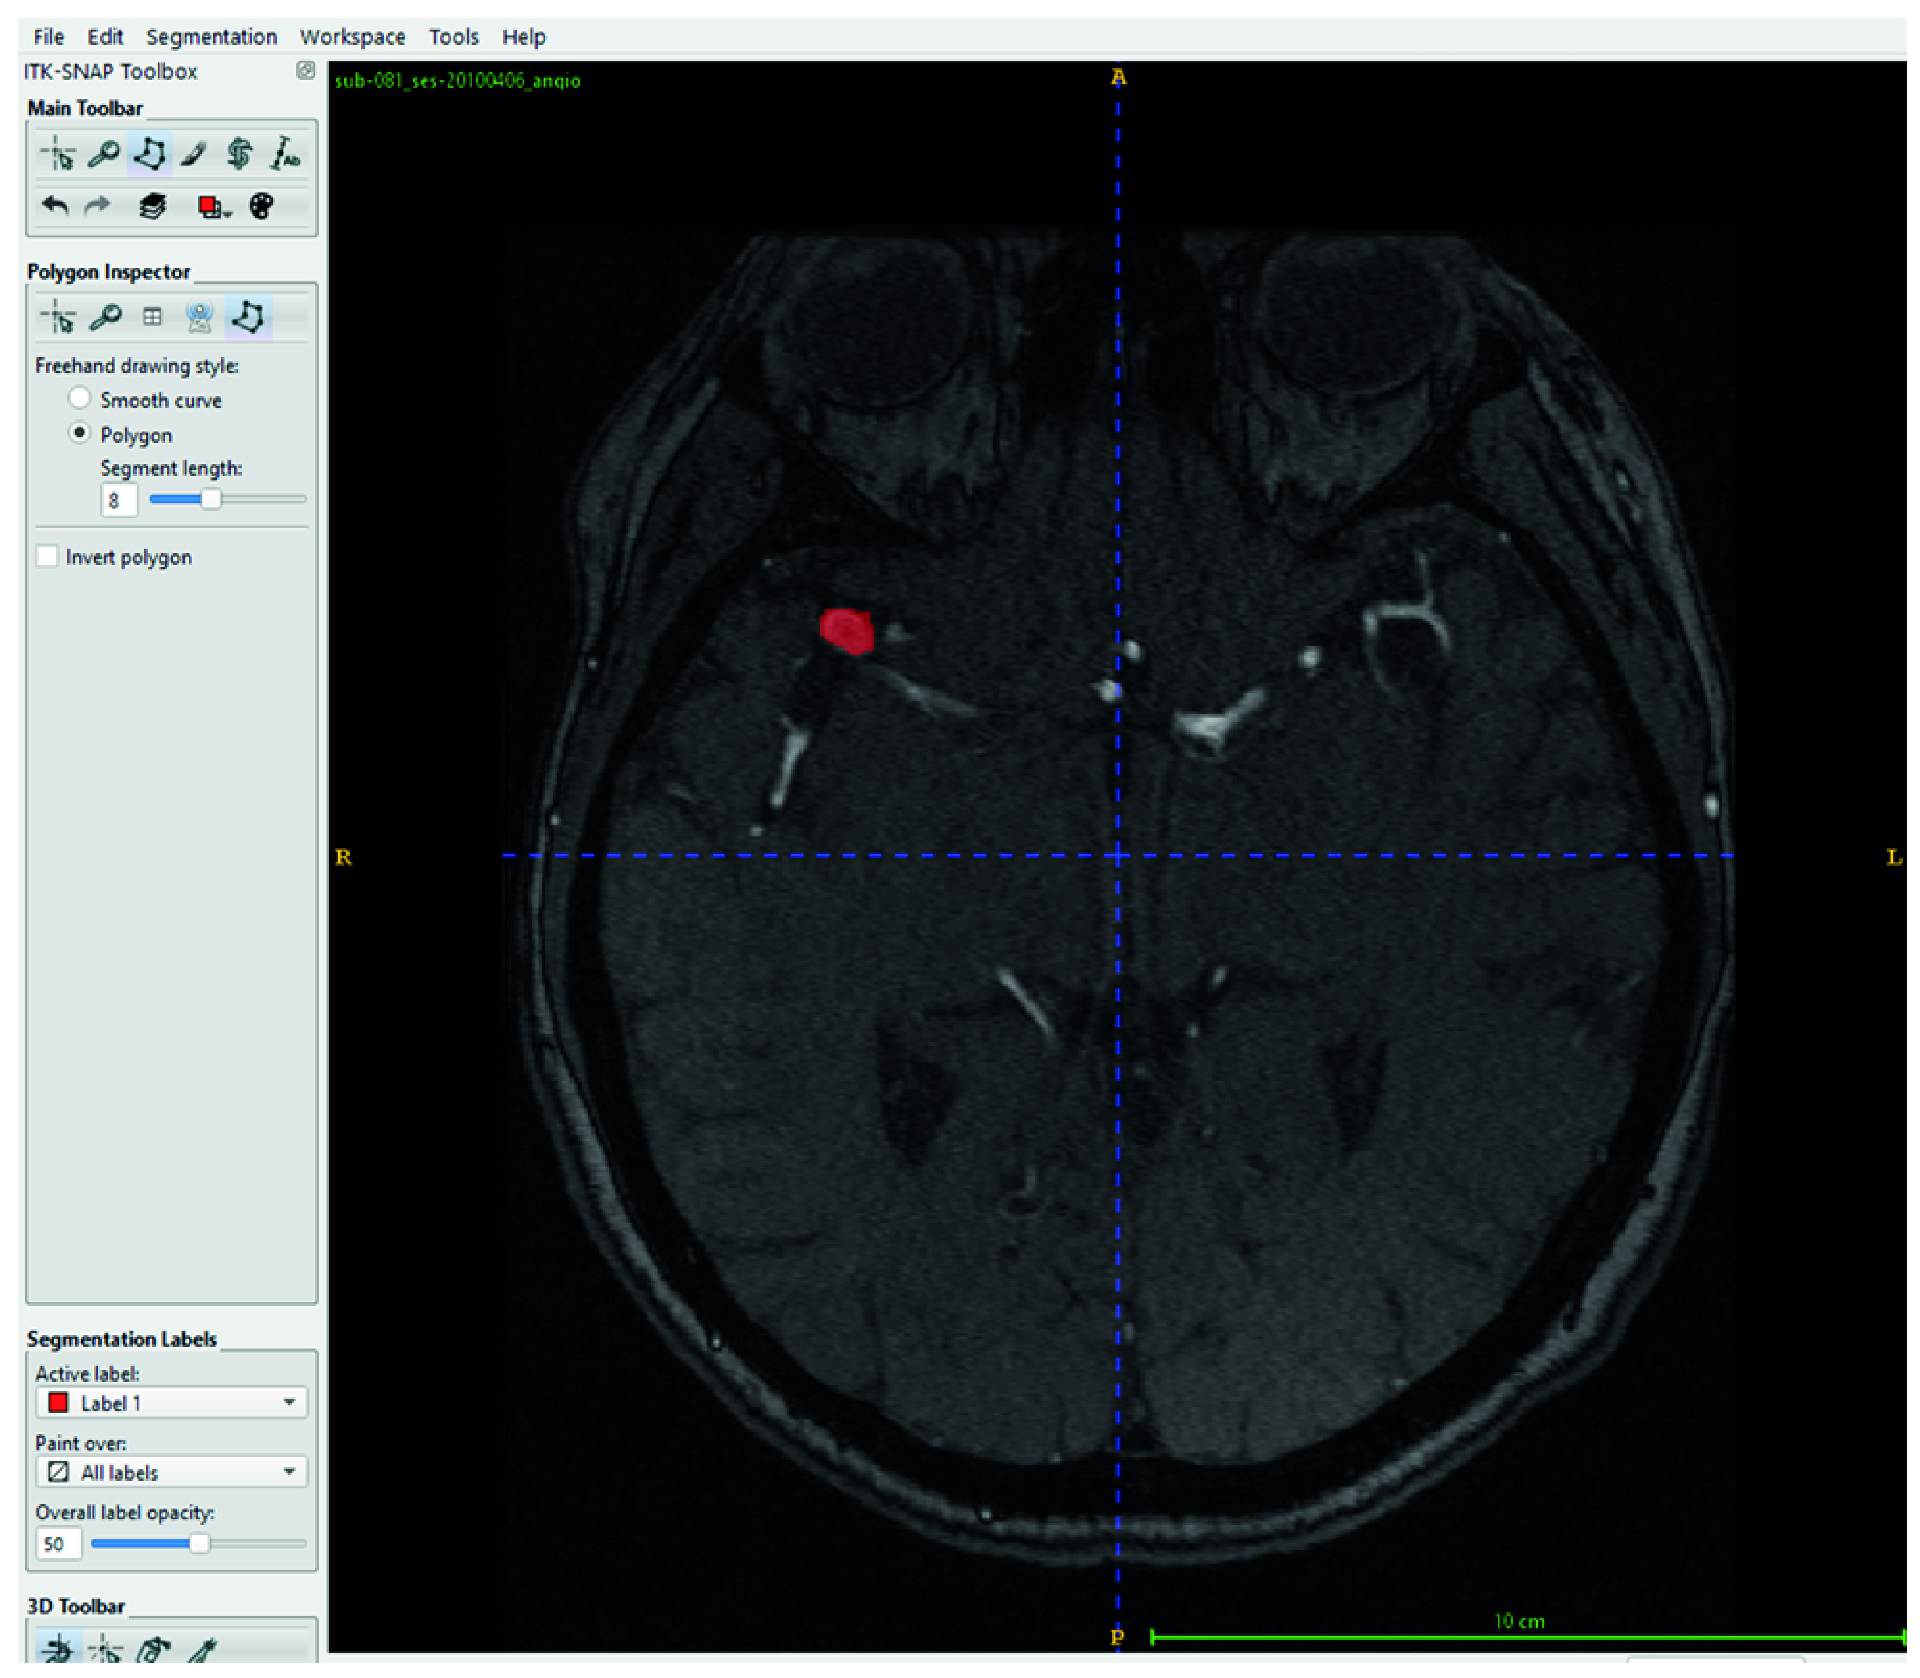

In this study, several preprocessing steps were applied to prepare the TOF-MRA images for deep learning. To focus the model on intracranial structures, skull stripping was applied to all TOF-MRA images using FMRIB’s Brain Extraction Tool (BET). By adjusting parameters such as fractional intensity and surface inflation, brain tissue was effectively isolated. Processed images were manually reviewed, and necessary adjustments were made to ensure accurate brain extraction, resulting in a clean dataset suitable for segmentation. The raw data consisted of 3D volumetric brain images stored in NIfTI format (nii/nii.gz). To improve the training performance of the model and standardize the dataset, these volumes were converted into two-dimensional (2D) slices and saved in PNG format. Each image slice was then paired with its corresponding segmentation mask (Figure 2).

One of the most important steps in the preprocessing workflow was the conversion of 3D volumetric TOF-MRA images into two-dimensional slices. Each TOF-MRA sequence was sliced in the axial plane and converted into 2D images, with each slice saved as an individual image file. The same process was applied to the segmentation masks, ensuring that each aneurysmal region was paired with the corresponding 2D image.

Figure 2. Sample 2D slices and corresponding aneurysm masks derived from TOF-MRA volumes. Left (a,c): Binary segmentation masks showing aneurysm regions in white. Right (b,d): Original TOF-MRA slices corresponding to each mask. Each 3D volume was converted into 2D axial slices, and manual annotations were used to generate ground truth segmentation masks.